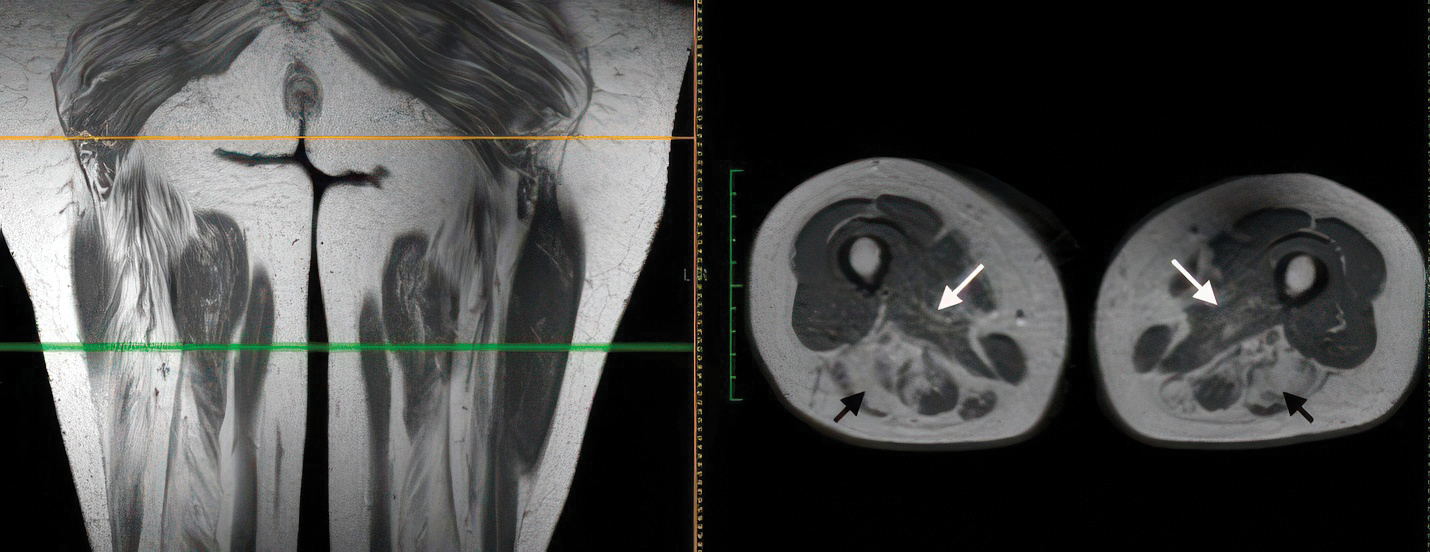

Пациентке было выполнено магнитно-резонансное томографическое исследование (МРТ) мягких тканей правого и левого бедра. Получены данные о симметричной жировой дистрофии мышц заднего компартмента бедра (полуперепончатая, полусухожильная, двуглавая мышцы) и больших приводящих мышц бедра без признаков отёка, поражения жировой клетчатки, фасциальных футляров и сосудисто-нервных пучков (рис. 3).

Рис. 3. Результаты МРТ мягких тканей бёдер пациентки А. (режим Т1-ВИ, фронтальный и аксиальный срезы).

Определяется выраженная симметричная жировая дегенерация задней группы мышц бедра (чёрная стрелка) и умеренно выраженная жировая дегенерация больших приводящих мышц бедра (белая стрелка).

При МРТ мышц бёдер у обследуемой пациентки обращала внимание значительно более выраженная жировая дегенерация задних мышц бедра по сравнению с медиальными, что может быть расценено как индивидуальная особенность.